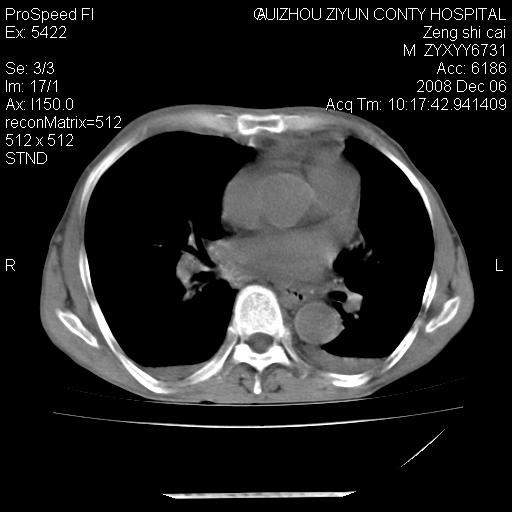

标题: CT16961:M、71岁,咳嗽半年,无血痰;胸片示右肺占位。 [打印本页]

标题: CT16961:M、71岁,咳嗽半年,无血痰;胸片示右肺占位。

右肺癌并纵隔淋巴结及胸膜转移可能性大

右肺癌并纵隔淋巴结及胸膜转移。建议气管镜

右肺纵隔型肺癌伴纵隔淋巴结及胸膜转移!

右肺纵隔型肺癌伴纵隔淋巴结转移!双侧胸水!

1)考虑右肺上叶纵隔型肺癌伴纵隔淋巴结转移。2)心包积液,双侧胸腔积液。

右肺癌并纵隔淋巴转移,腹膜后转移可能性大,两侧胸腔积液

右肺癌并纵隔淋巴结及胸膜心包转移,好多团团点点,看得有点想吐

右肺上叶纵隔型肺癌伴纵隔淋巴结转移。心包积液,双侧胸腔积液。

右上肺癌并纵隔淋巴结及胸膜转移。

右肺纵隔型肺癌伴纵隔淋巴结转移!双侧胸水\\心包积液

建议强化!主要鉴别是淋巴瘤与肺癌淋巴结转移。

右肺纵隔型肺癌伴纵隔淋巴结及胸膜转移